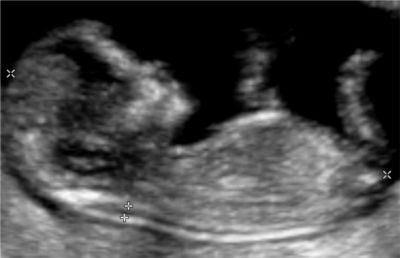

Echographie obstétricale

La surveillance d’une grossesse normale nécessite la pratique de 3 examens échographiques à 12 semaines, 22 semaines et 32 semaines d’aménorrhée en plus de la surveillance mensuelle par votre médecin.

C’est une technique qui utilise les ultrasons. Dans les conditions d’utilisation médicale aucun risque n’est connu. L’échographie Doppler repose sur le même principe. On analyse la circulation sanguine fœtale, placentaire et de l’utérus maternel afin d’évaluer la qualité des échanges materno-fœtaux et le bien être fœtal.